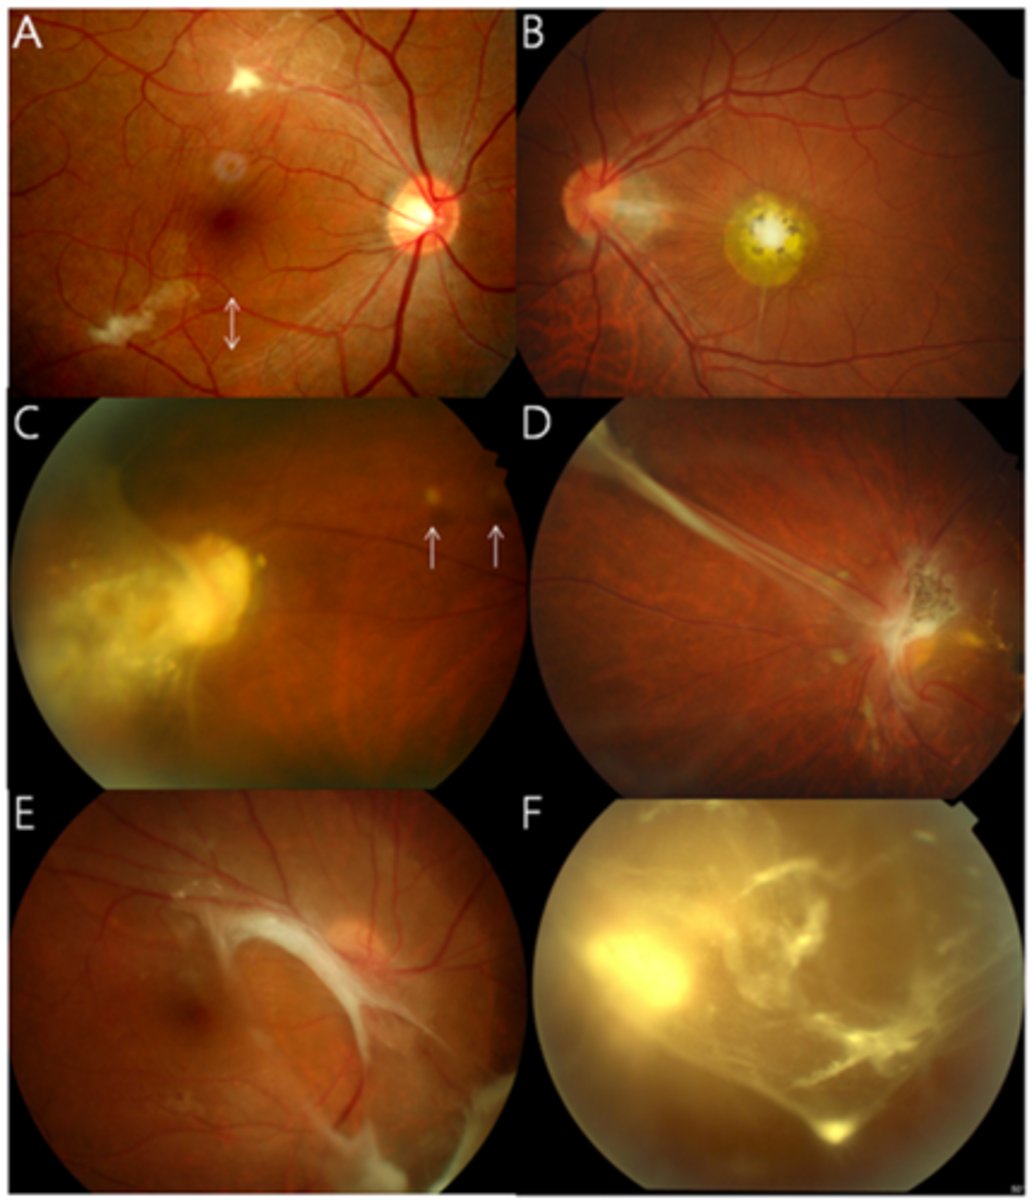

tesselated or tigroid fundus = visibility of choroidal vasculature (A)

What are some common findings in degenerative myopia?

lacquer cracks (C)

CNV (E)

chorioretinal atrophy (B)

What findings of degenerative myopia are seen here?

PPA

crescent

lacquer cracks

How do lacquer cracks appear on fundoscopy?

jagged, irregular yellow lines showing sclera in the posterior pole